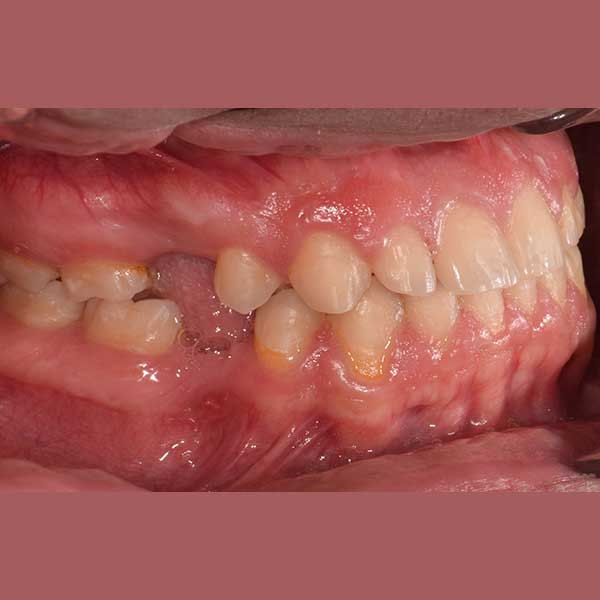

BEFORE

My friend here has suffered from the early loss of some permanent back teeth, which led to the creation of spaces between the front teeth and the inability to place dental implants to replace the missing teeth due to the small spaces between the front teeth.